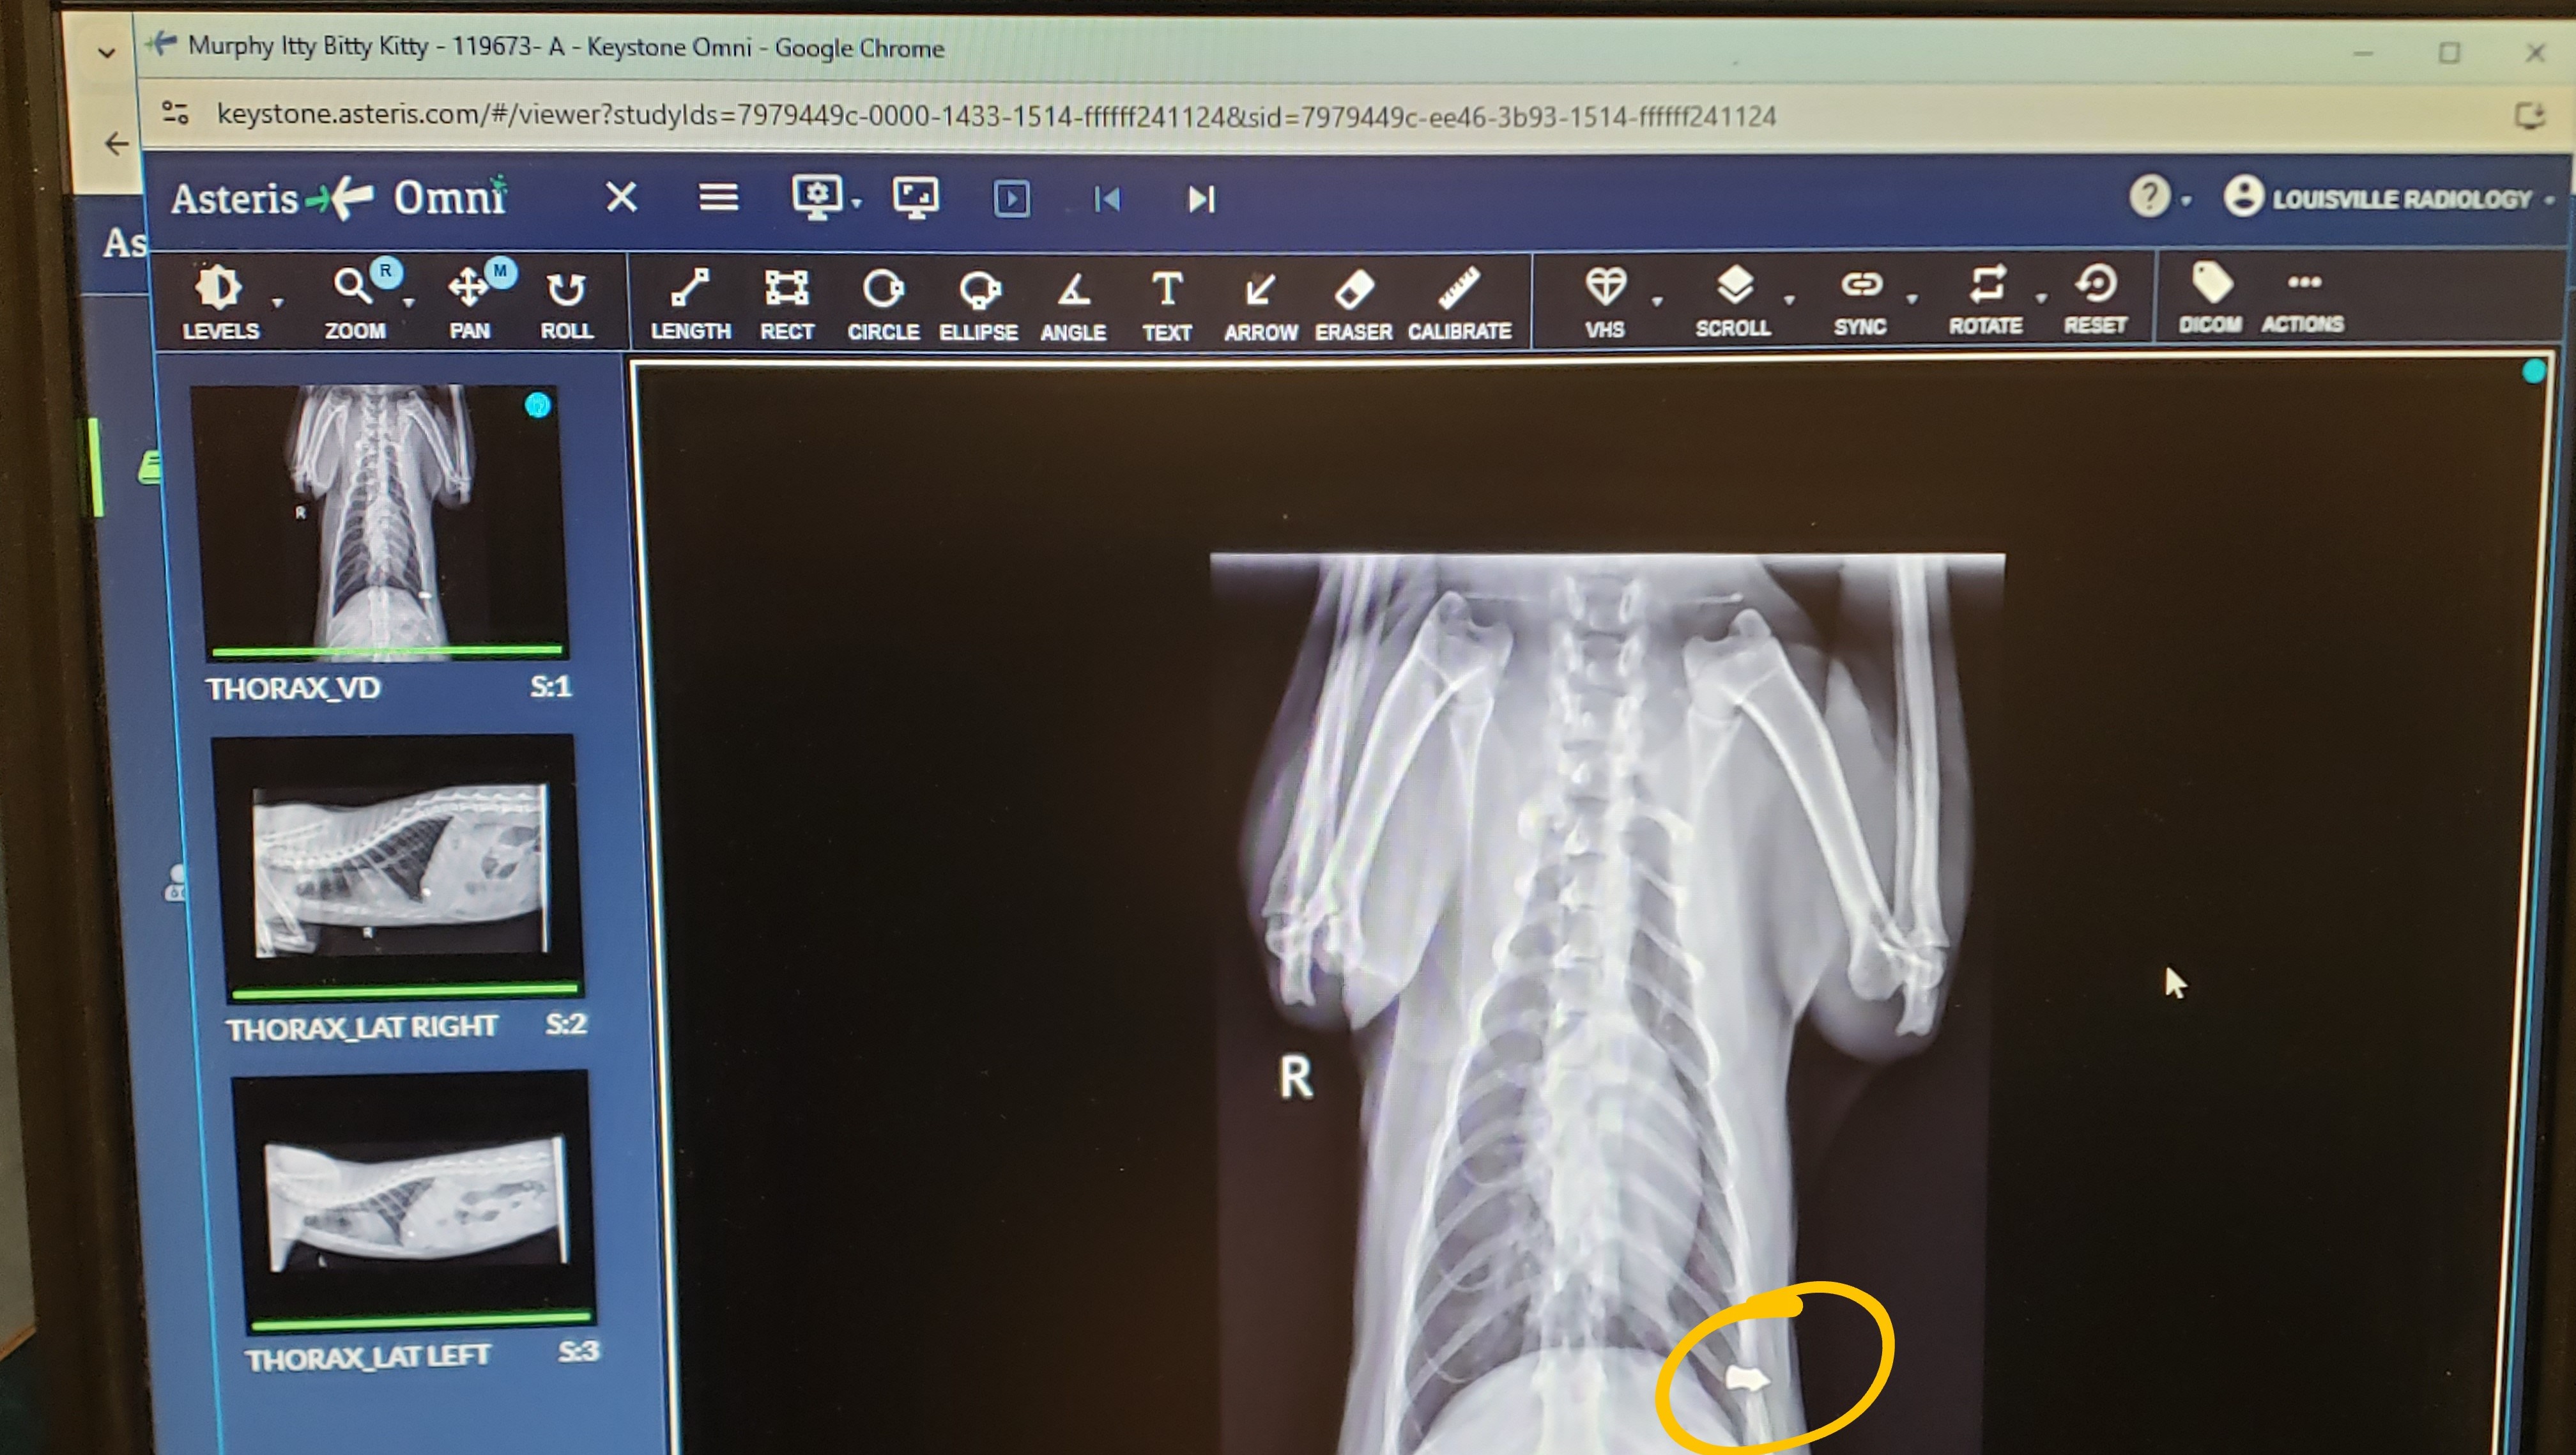

My cat came home that morning bleeding profusely from a wound on his side. When I couldn't get the bleeding to stop, I rushed him to the emergency animal hospital in Louisville. They cleaned the wound, took an x-ray, gave him a shot of antibiotics, and applied some pain medicine. $1200 later, I was informed that it appeared as tho he was targeted by someone that clearly intended to kill him (because of the type of ammunition used), but that he was "very lucky" because it missed his heart and his lungs. Which got me thinking: I have another cat that went missing on November 2nd, which is highly unlike her to not come home; what are the odds that something unrelated happened to both of my cats only a few weeks apart? I feel that it is highly unlikely for that to be the case. What I think happened, is that my other cat wasn't so "lucky", which breaks my heart to think about. Why would someone target my cats with the intention to kill them?! If they were bothering you somehow, why not come talk to me about it? Whatever happened to being "neighborly"?